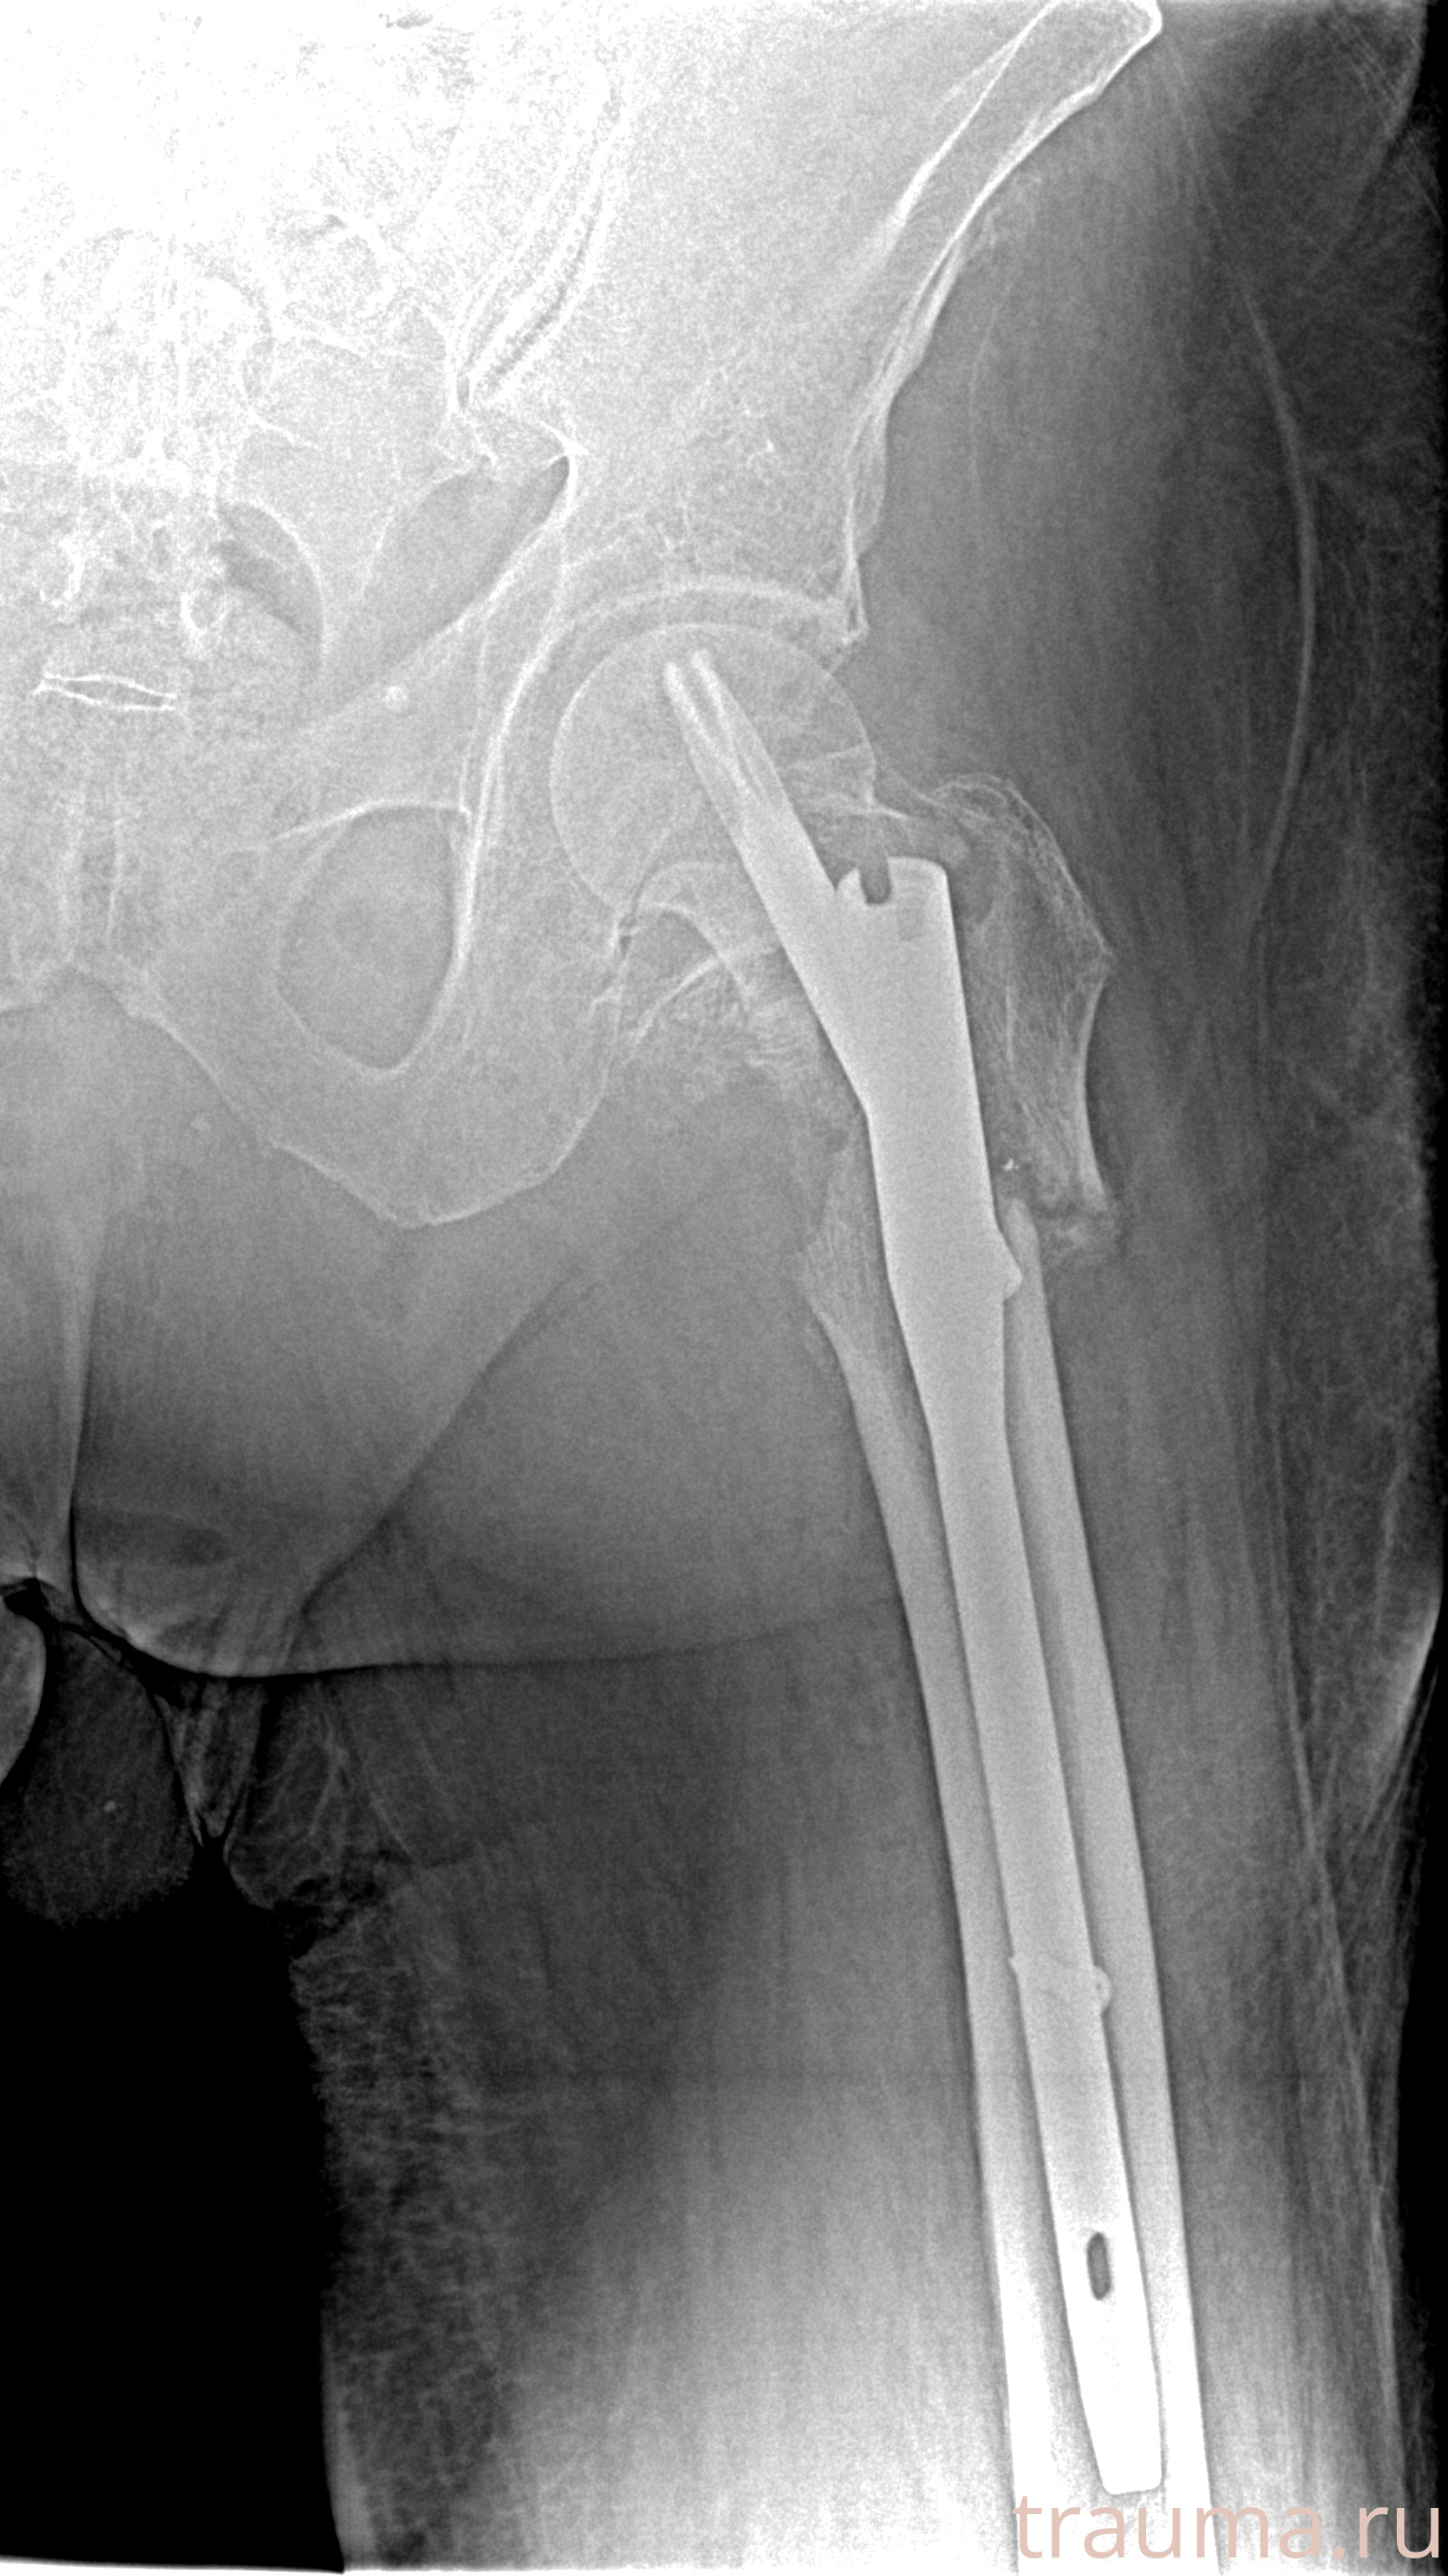

Рентгенограммы